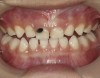

Fig 6. Use of 38% SDF to arrest root caries in permanent teeth of an elderly patient. Fig 6: The arrested root carious lesions were hard to probe.

Figure 6

Fig 7. The lower incisors were responsive to electric pulp testing with no radiographic pathology.

Figure 7